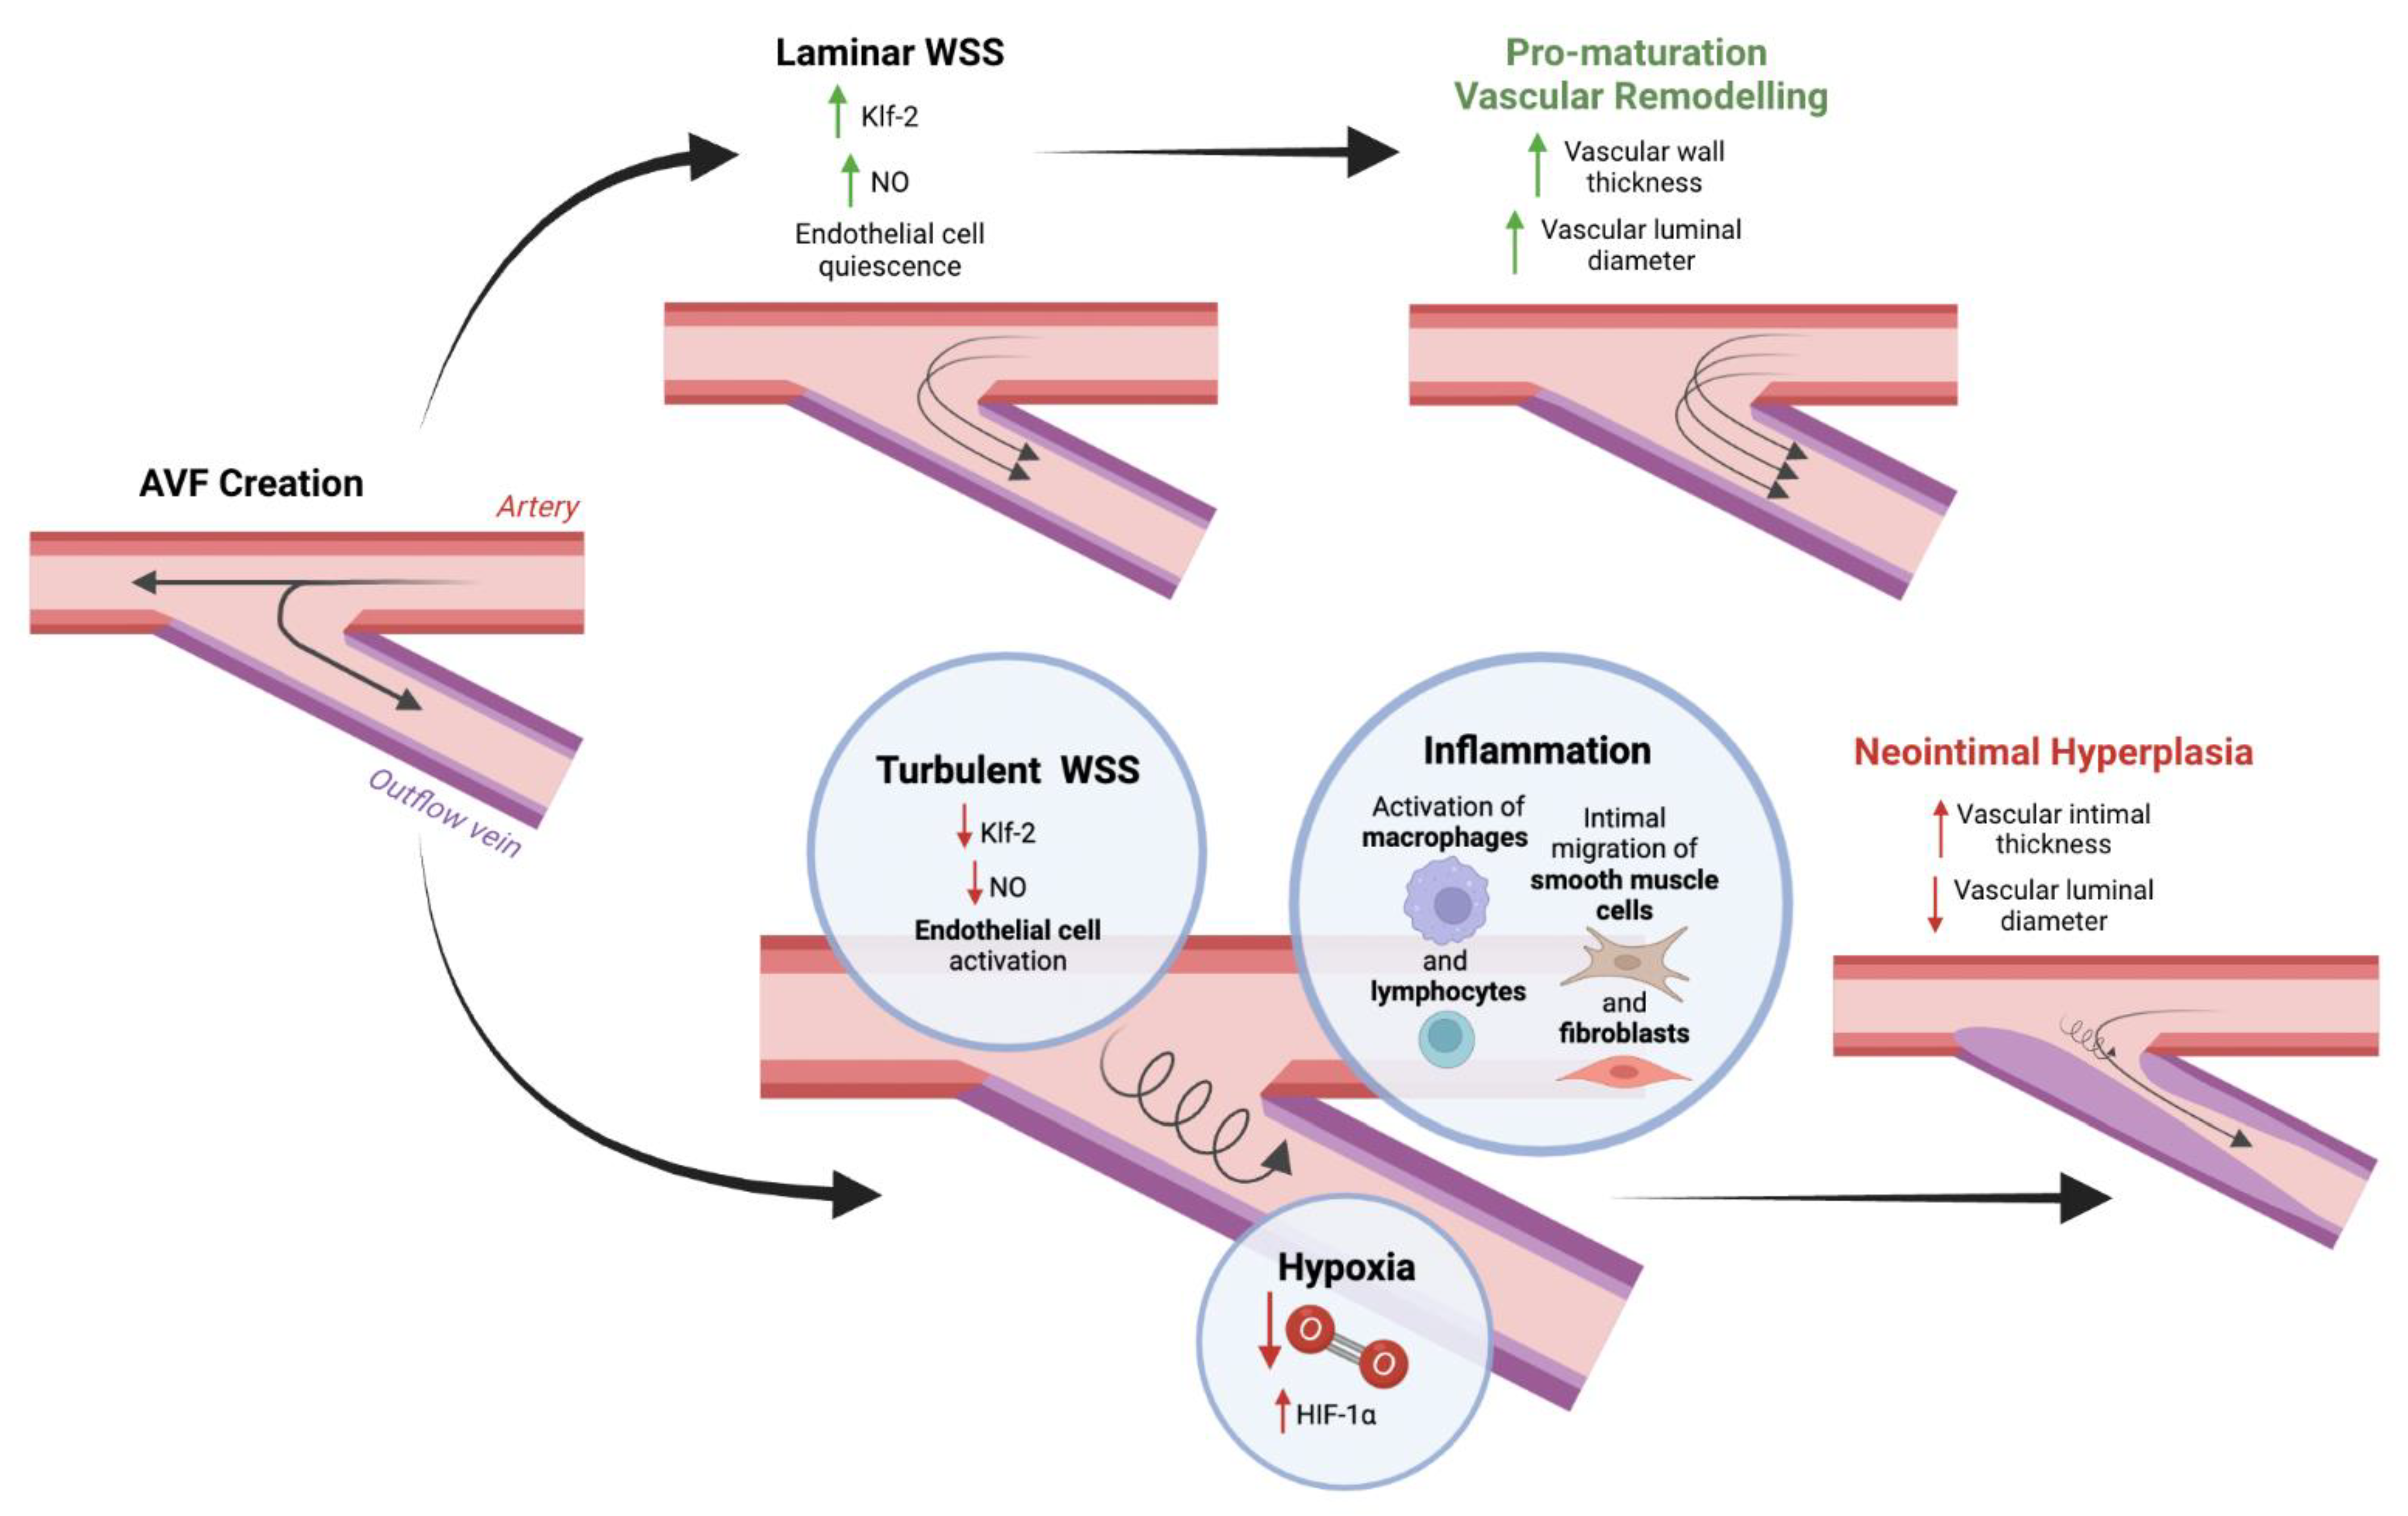

2. Pathophysiology of Venous Neointimal Hyperplasia

2.1. AVF Creation and the Physiology of Maturation

2.2. Pathways That Lead to Venous Neointimal Hyperplasia